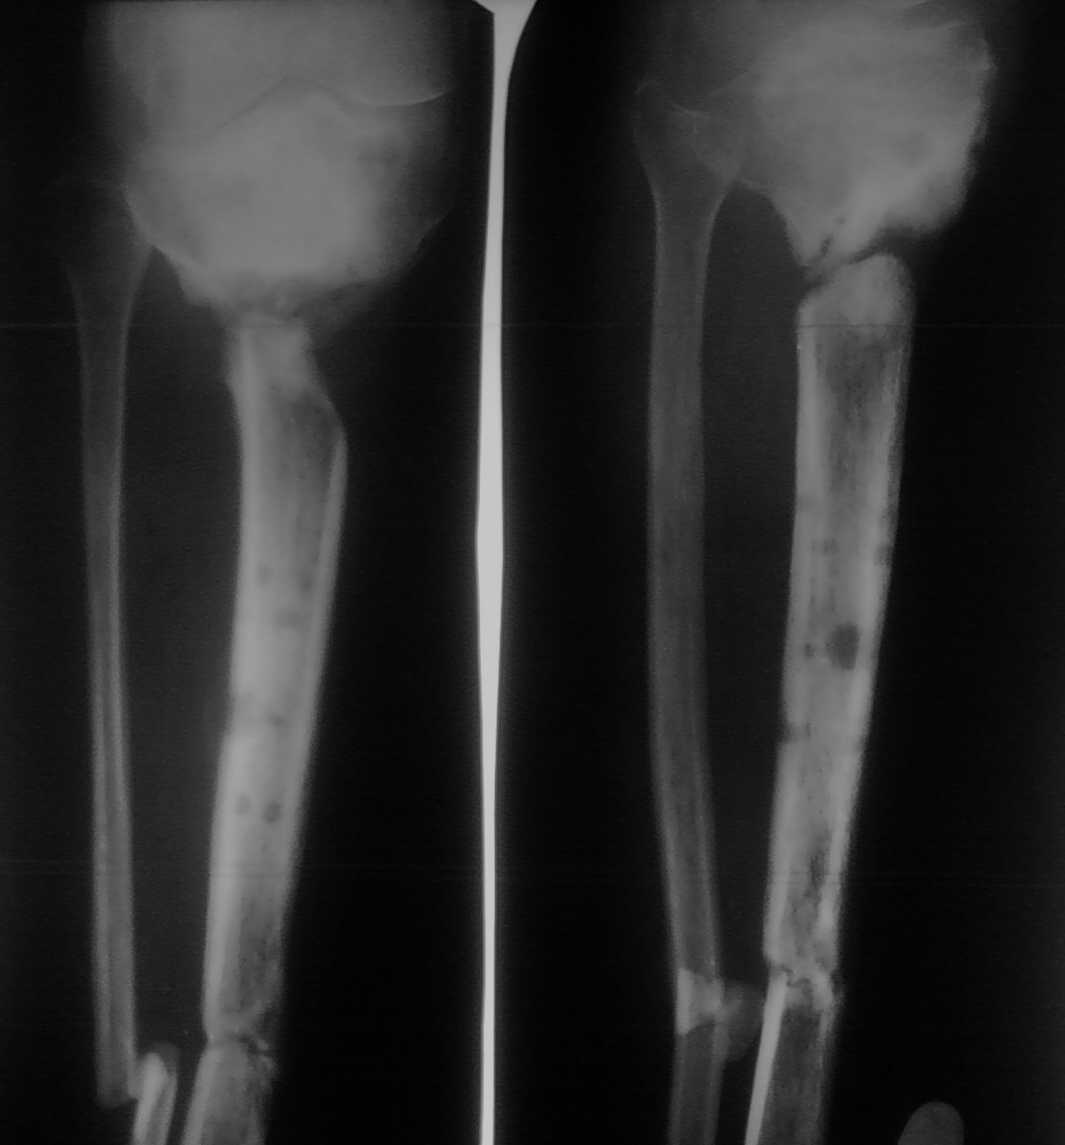

Помогите определиться с тактикой лечения пациента с застарелым переломом голени

Больной лечится уже год. Первоначально был открытый перелом дистальной части костей голени и закрытый - в проксимальной части большеберцовой кости. Больного вели на аппарате внешней фиксации. Результат - на снимке.

Какую тактику лучше избрать в данном случае?